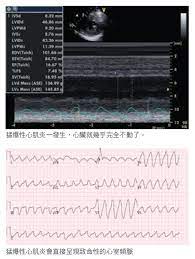

急性心肌炎是隱藏殺手 符合ï¼

急性心肌炎是隱藏殺手 符合ï¼"症狀要警覺 from s.yimg.com